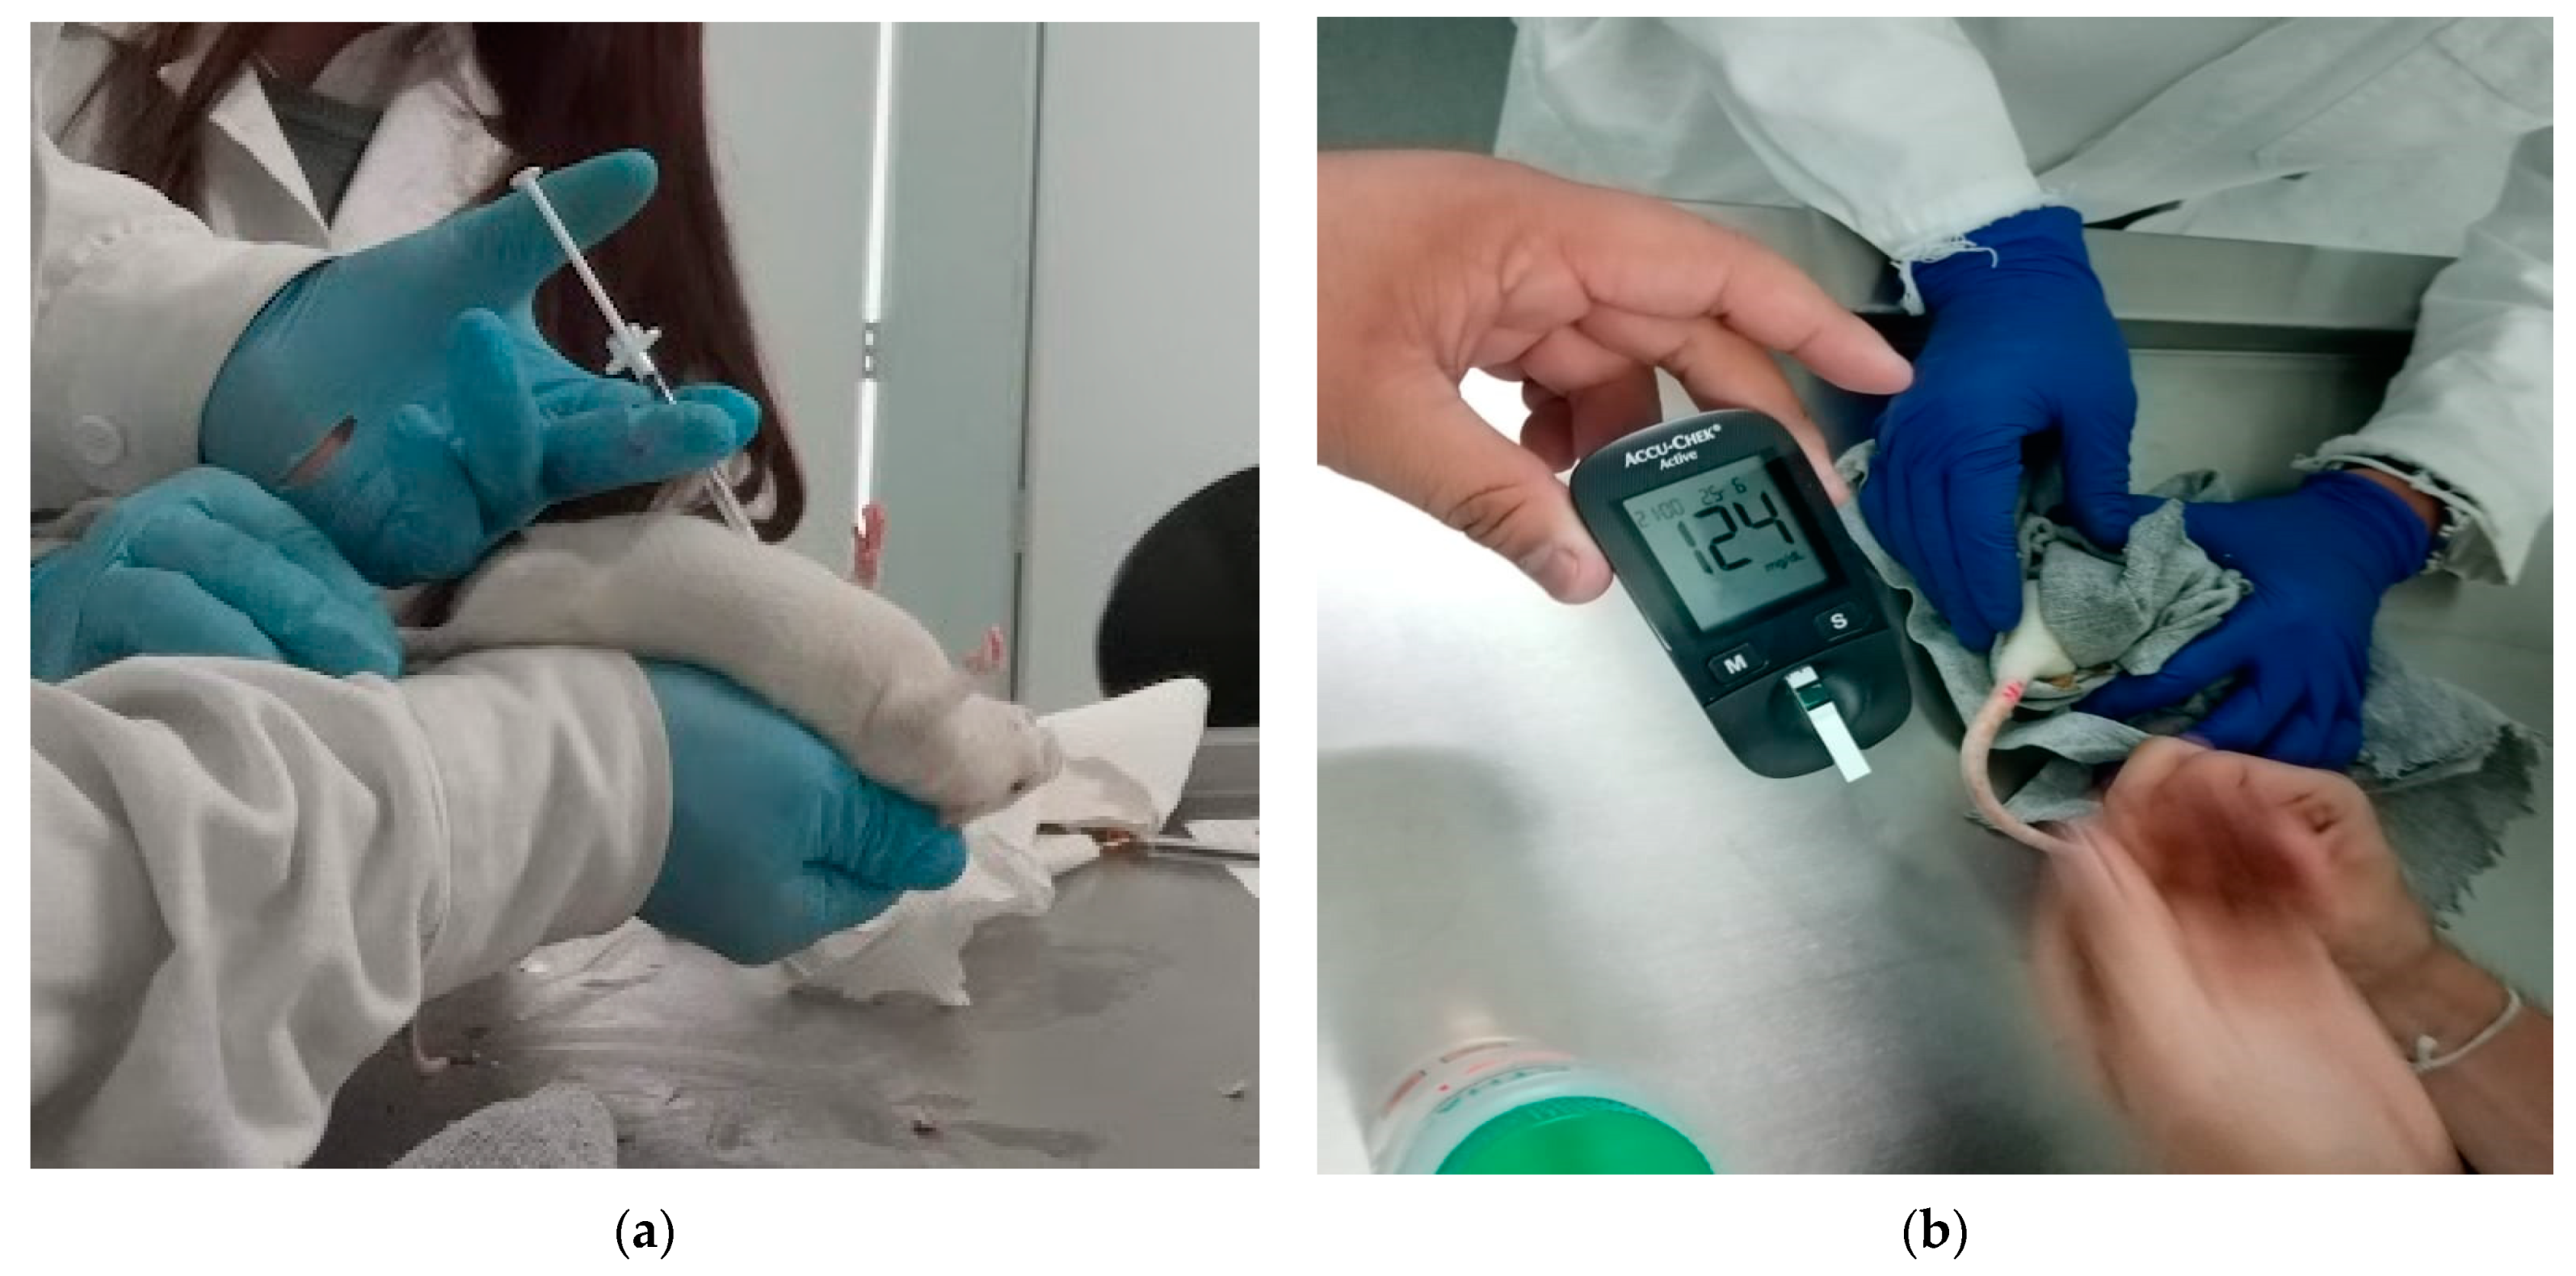

2.7. In Vivo Model

3.1.7. In Vivo Tests